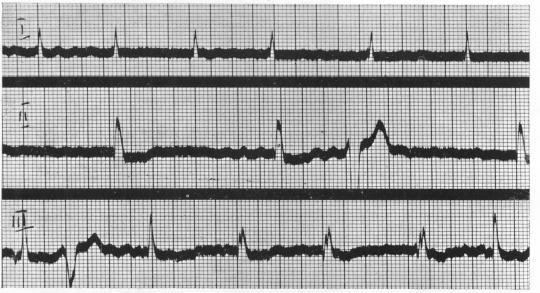

INCOMPLETE BUNDLE BRANCH BLOCK.

Br Heart J. 1944 Jul;6(3):139-48. doi: 10.1136/hrt.6.3.139.